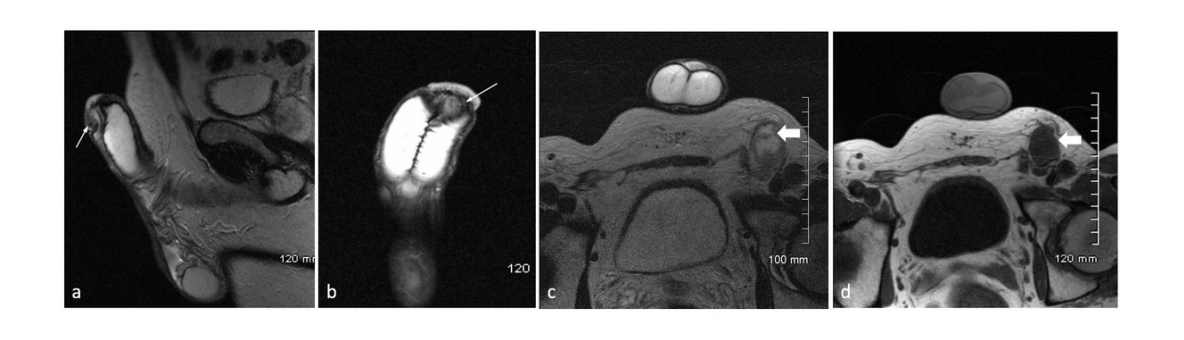

Phương pháp chụp cộng hưởng từ không sử dụng thuốc đối quang hiển thị rõ các cấu trúc giải phẫu của vùng bẹn, bìu, dương vật. Ngoài ra, có thể phát hiện được tổn thương ở các khu vực này nếu có.

Chụp cộng hưởng từ bìu, dương vật có tiêm thuốc cản từ ngoài mục đích khảo sát hình thái và tổn thương còn nhằm đánh giá tình trạng tưới máu của các cấu trúc, tổn thương của cơ quan sinh dục ngoài của nam giới.

Cũng giống như chụp cộng hưởng từ không sử dụng đối quang, hình ảnh chụp bằng phương pháp hiển thị rõ các cấu trúc giải phẫu của vùng bẹn, bìu, dương vật, đồng thời phát hiện được các tổn thương nếu có và đặc điểm ngấm thuốc đối quang từ.